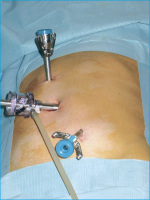

Die roboterassistierte laparoskopische Pyeloplastik analog Anderson-Hynes

Journal für Urologie und Urogynäkologie 2006; 13 (4) (Ausgabe für Österreich): 14-16 Journal für Urologie und Urogynäkologie 2006; 13 (4) (Ausgabe für Schweiz): 14-16 Volltext (PDF) Summary Abbildungen